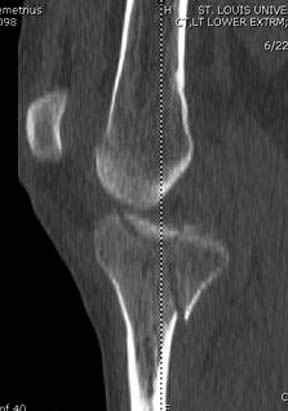

Пациенту сделали КТ - ухитрились сделать на шине Белера (не давал положить прямую ногу) - срезали передний отдел. Планируется на пятницу (24.12) на операцию - синтез длинной мыщелковой LCP-пластиной Synthes :). Отек ближе к слову умеренный (окружность голени +4 см по сравнению со здоровой). КТ и снимок на вытяжении прилагаются.

Здесь как раз тот случай, когда результат зависит не только от мастерства хирурга, но и от наличия современных методов исследования. Например, КТ которая поможет рассчитать направления шурупов и установку импланта. Кроме этого, поможет определиться с доступом.

На представленных предоперационных срезах КТ огромный задне-медиальный фрагмент расположен больше кзади, чем медиально. Для планирования, кроме поперечных срезов, надо ориентироваться на корональные срезы, которые укажут топографию верхушки медиального фрагмента.